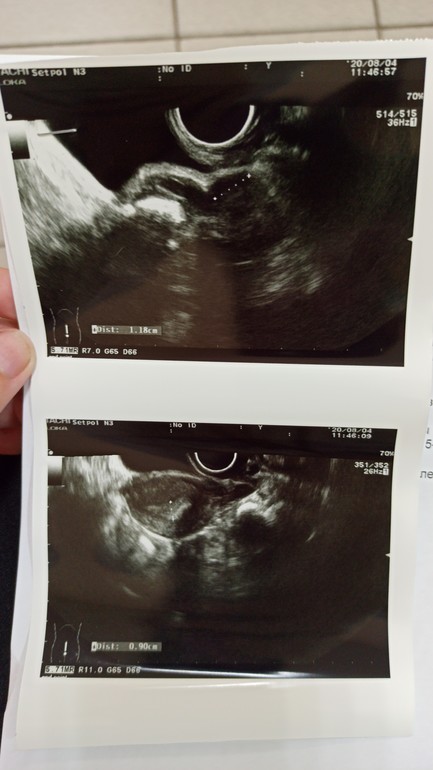

Спросила из-за жт, 12 мм, при таком бер?) просто чаще вижу, что 13-16 хотя бы...

Я жду Б, это да. А интересует меня жт... При 12 мм у кого-то начиналась Б и как все было)

Меня смущает желтое тело.. Оно не должно быть больше на 24 дц

Ну размер ЖТ не показателен, важнее его функциональность, наличие кровотока. У Вас, кстати, если нет Б, то ЖТ уже и регрессировать может, вполне возможно, что сразу после О оно побольше было.

Сказали кровоток нормальный, но я тоже думаю за регресс. Так как тесты пустые

28-30..вроде как. Но бывают перебои.. 26 и больше 31 ... И свой прогик маленький. Так что может. Хотя по словам врача кровоток хороший, и может влиять, что может врач недомерила... Я смотрю хвостик как будто чуть дальше уходит)